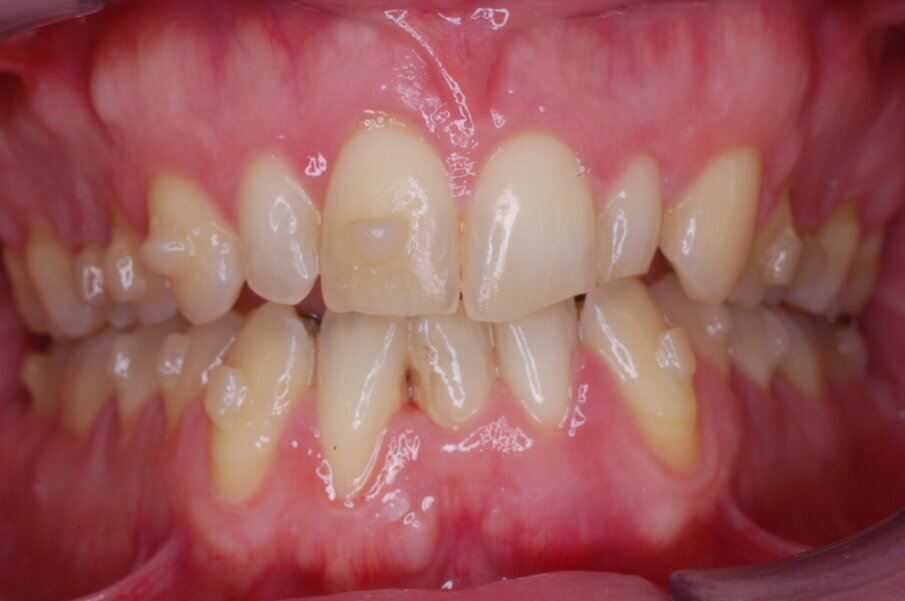

Diagnosi ed eziologia Un uomo sano di 39 anni si è presentato nel nostro studio ortodontico lamentando un aspetto dentale poco attraente e la paura della chirurgia ortognatica proposta da un altro ortodontista. Clinicamente, il profilo del paziente era rettilineo e la vista frontale non mostrava alcuna asimmetria facciale. L’esame funzionale non ha rivelato alcuna deviazione mandibolare o riduzione dei movimenti. Il paziente non aveva dolori articolari e non sono stati rilevati rumori articolari. Era presente una lieve occlusione molare bilaterale di Classe II, un morso aperto e un grave affollamento in entrambe le arcate. L’affollamento era particolarmente grave nell’arcata mandibolare, sebbene mancasse l’incisivo centrale mandibolare destro. Gli incisivi mascellari erano di piccole dimensioni, suggerendo una discrepanza dell’indice di Bolton se fossero stati presenti tutti e quattro gli incisivi mandibolari. Erano inoltre presenti un morso incrociato nella regione dell’incisivo laterale superiore sinistro e una grave rotazione distale del secondo premolare mandibolare sinistro (Figg. 1-8).

Figg. 1-8_Fotografie facciali e intraorali pre-trattamento.